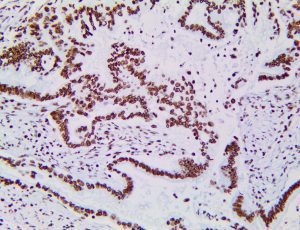

It is the ICU physician who is most likely to witness one of the deadliest manifestations of the abnormal immunological response, the cytokine storm syndrome (CSS). This response is also referred to by some as the cytokine release syndrome (CRS). CSS is characterized by continuous activation and expansion of macrophage and lymphocyte populations, which secrete large amounts of cytokines, causing the cytokine storm. This massive cytokine release is akin to hemophagocytic lymphohistiocytosis (HLH) disease, a syndrome characterized by initial unchecked and persistent activation of cytotoxic T lymphocytes and NK cells.

Clinical and laboratory manifestations of HLH include fever, enlarged liver and/or spleen, neurologic dysfunction, coagulopathy, liver dysfunction, cytopenias (i.e., low levels of erythrocytes, leukocytes, and/or platelets), hypertriglyceridemia, hyperferritinemia, hemophagocytosis, and eventually diminished NK cell activity as the immune system becomes progressively paralyzed. HLH can be familial (primary HLH) or secondary to another disease process (sHLH), such as rheumatic disease, in which it is referred to as macrophage activation syndrome (MAS, characterized by elevated ferritin).